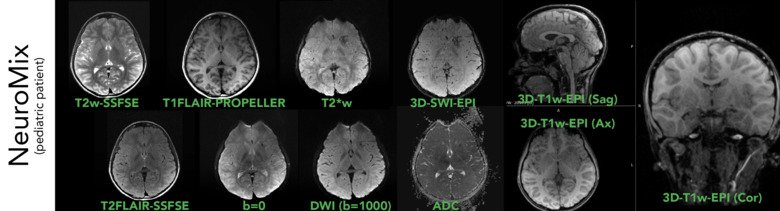

MR är en långsam bildtagningsmetod, där varje bildserie tar flera minuter att samla in, vilket ställer stora krav på patienten att ligga still. Forskargruppen har två större forsknings- och utvecklingsprojekt för att hantera detta. Det ena är ultrasnabb bildtagning som pulssekvensen NeuroMix, där de vanligaste MR-kontrasterna som behövs för en komplett hjärn-MR-undersökning erhålls i form av nio bildserier under 3 min.

Ultrasnabb (och rörelserobust) MR - NeuroMix

NeuroMix på en barnpatient, som första bildomgång i vårt pediatriska MR-protokoll. Med en scantid för NeuroMix på ~2:40 min, där 2D-kontrasterna är rörelserobusta och kan registreras mot varandra i rekonstruktionen, blir dessa bilder oftast bra även i närvaro av större huvudrörelser. Med framtida integration med WRAD & Tracoline kommer NeuroMix bli ännu mer robust mot huvudrörelser.